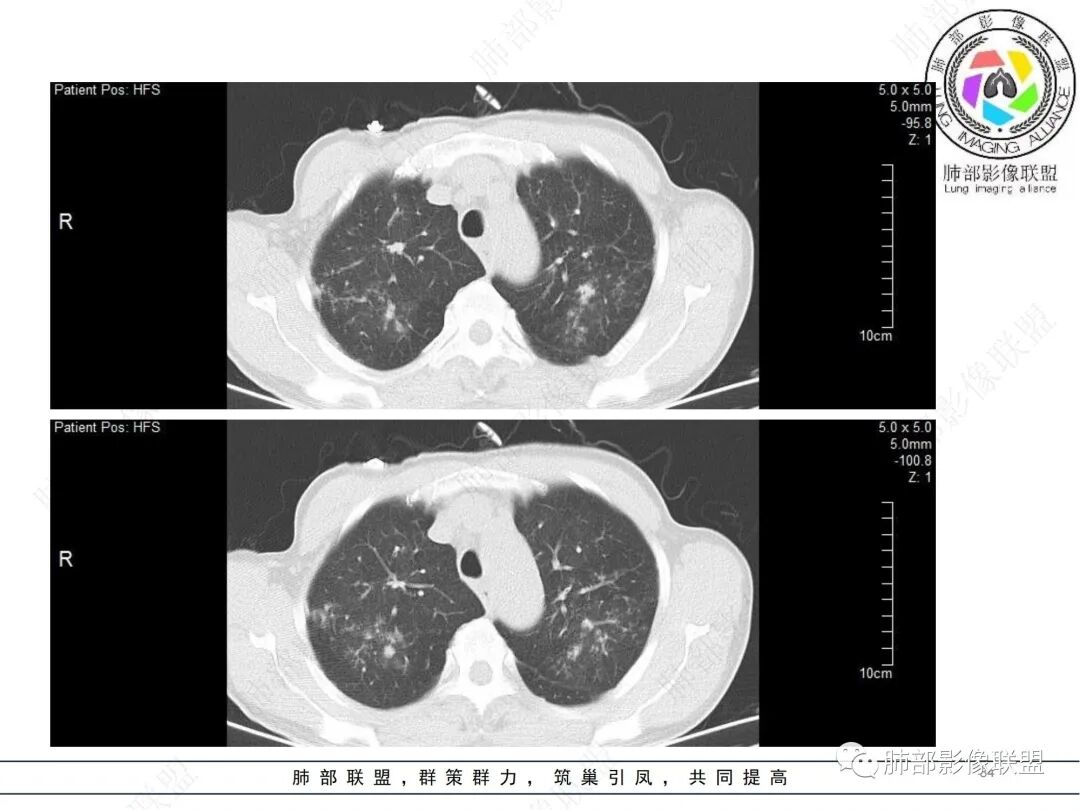

58岁男性,咳嗽胸闷3天,咳较多褐粘液痰,无发热。有2型糖尿病病史。白细胞与中性粒细胞升高。CRP升高。鳞状上皮细胞癌抗原轻度升高。结核T细胞免疫斑点实性阳性。肺炎支原体、衣原体IgG轻度升高。支气管镜显示支气管炎性改变、右肺下叶背段管腔狭窄。2.影像特点:

2022.6.24CT显示两肺弥漫性段、亚段支气管壁增厚(两肺各叶都累及),增厚的支气管壁外可见沿着支气管分布的渗出、实变影。另外远端肺内亦可见多发树芽影、结节影,其边界欠清晰。右肺下叶基底段局部胸膜下亦可见小斑片影,边界不清。2022.6.27CT显示两肺增厚的支气管壁外的渗出实变影明显增多、范围更广。远端肺内病灶亦增多、范围增大。部分位于胸膜下的病灶可见侧向融合趋势。3.病例分析: